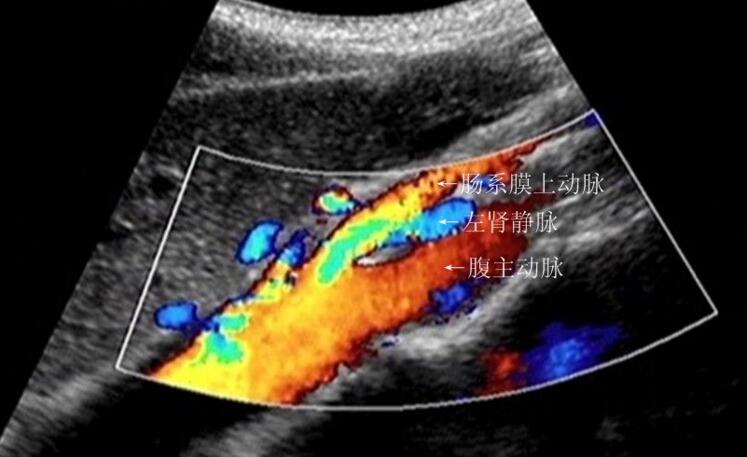

今日诊断一例【胡桃夹综合征】#超声影像 腹主动脉之间夹角变 - 抖音

p>胡桃夹现象(nutcracker phenomenon)亦称左肾静脉压迫综合征,好发

征(nutcracker syndrome,ncs),即左肾静脉压迫综合征,又称胡桃夹现象